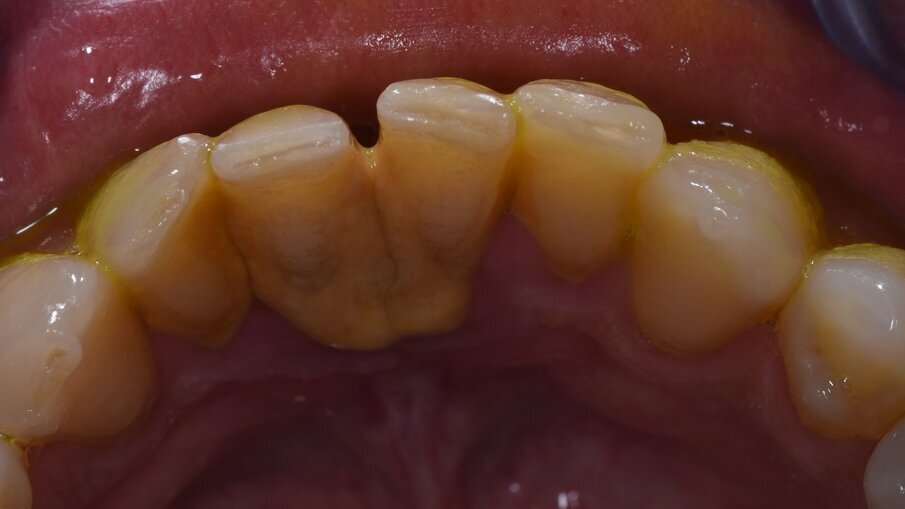

Vengono rilevati gli indici clinici e vengono condivise con il paziente le immagini raccolte con la videocamera intraorale, così da motivarlo di fronte alla presenza di tartaro e infiammazione gengivale e mostrargli le aree critiche. Viene apposto il rilevatore di placca alla fluorescina ed illuminato da una lampada fotopolimeralizzante, che permette di visualizzare la topografia del biofilm batterico (D-BIOTEK-TECNICHE)2, in modo da condividere con il paziente i siti più a rischio del cavo orale (Figg. 1a-2f).